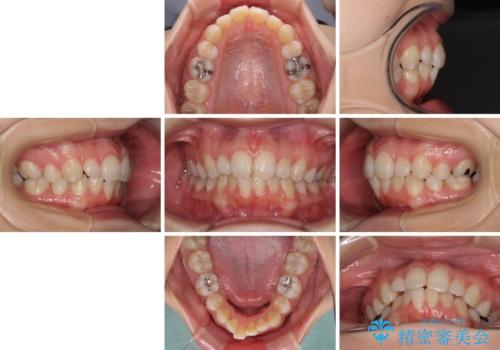

インビザライン・ライトで抜歯矯正の後戻りを解消

- 下顎前歯を中心に、以前行った矯正治療の後戻りが気になるとのことで来院された患者様です。

後戻りは軽度であったため、インビザライン・ライトにて治療を行うこととしました。

治療途中で出産をされたため、通院が困難となりましたが、インビザライン・ライトでの治療可能期限である2年以内に無事に治療を終えることができました。